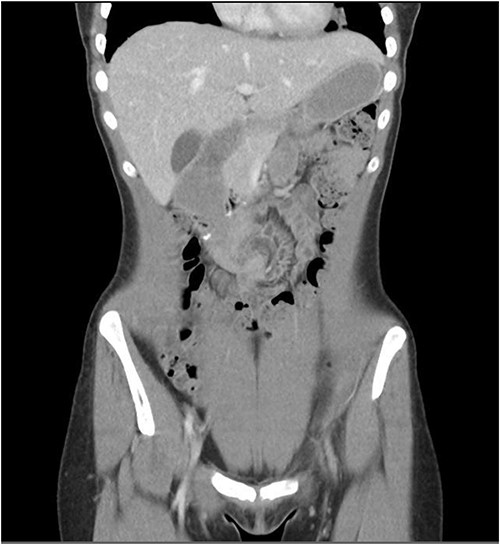

She presented to the surgeon’s rooms with a history of 9 days of postprandial vomiting 9 months later. A computed tomography (CT) showed a volvulus immediately adjacent to the duodenojejunostomy anastomosis causing a small bowel obstruction (Fig. 2).